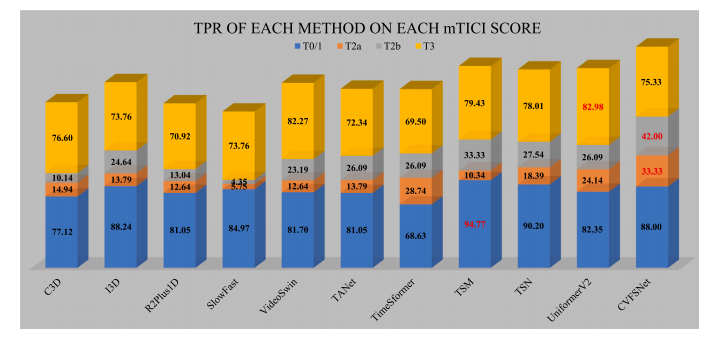

Fig. 7. TPR of each method on each mTICI score of AmTICIS, and the best results are indicated in red.

图7:在自动改良脑梗死溶栓分级评分(AmTICIS)数据集的每个mTICI评分等级上,各方法的真阳性率(TPR),最优结果以红色标出。

We proposed a CVFSNet based on dual-view angiographic imagesfor automatic, objective, end-to-end mTICI scoring and built a crossview fusion module, CVFM, to integrate, aggregate, and complementfeatures from different views. In the ablation experiments, we firstcompared the performance between single-view and dual-view inputs,demonstrating the necessity of dual-view image input. This may bedue to the fact that DSA imaging is projection-compressed and intracranial vessel structures are complex, leading to vessel overlap insingle-view images, which affects the model’s ability to characterizeblood flow accurately. Then, by comparing different methods of dualview feature fusion, we verified the effectiveness of the CVFM module.CVFM leverages prior positional knowledge of coronal and sagittalviews, constructs oblique sagittal features using trigonometric functionsand the Pythagorean theorem, and employs a transformer-like moduleto explore complementary relationships between coronal and sagittalfeatures, thereby building global dependencies and generating more expressive fused features, ultimately enhancing performance. In the comparative experiments, we compared our approach with some classicaland state-of-the-art video feature classification models, demonstratingsuperior performance andgood stability.In the dichotomized experiments, CVFSNet demonstrated performance exceeding 90% across all indicators, implying that CVFSNet mayhave the potential for clinical application in determining the adequacyof mTICI scores. However, our study also has limitations. Firstly, thesevideo feature classification methods that were compared in the comparative experiments only supported single-view inputs, which maydisadvantage their comparison in terms of performance. Additionally,the AmTICIS dataset constructed in this study only includes data forM1 segment stenosis, limiting its clinical applicability. In the future,we plan to expand the dataset to include more mTICI scoring datawith various vessel stenosis, such as Internal Carotid Artery (ICA), BaseArtery (BA), Anterior Cerebral Artery (ACA), and Posterior CerebralArtery (PCA) etc., thereby constructing a more comprehensive scoringdataset. Also, the sample size of AmTICIS can be further expanded byincorporating data from multiple centers to enhance its diversity.In conclusion, we propose a novel CVFSNet in this paper for automatic, objective, and end-to-end mTICI scoring. Specifically, CVFSNetemploys dual branches to simultaneously extract spatial–temporal features from coronal view and sagittal view, and these cross-view featuresare fused through a novel cross view fusion module that explores thepositional characteristics of coronal and sagittal views to fuse andgenerate a pseudo-oblique sagittal feature and deploys a transformerlike architecture to explore the correlation between different viewfeatures, ultimately constructing more representative features to enhance the scoring performance of the model. In addition, we providea newly collected and the first publicly available digital subtractionangiography image dataset with expert annotations (AmTICIS) for automatic mTICI scoring, which can effectively promote researchers toconduct studies of ischemic stroke based on DSA images and finallyhelp patients get better medical treatment. Extensive experimentationresults demonstrate the promising performance of our methods and theeffectiveness of the cross-view fusion module.

我们基于双视角血管造影图像提出了CVFSNet网络,用于实现自动、客观、端到端的脑梗死溶栓治疗改良分级(mTICI)评分,并构建了一个跨视角融合模块(CVFM),以整合、聚合和补充来自不同视角的特征。在消融实验中,我们首先比较了单视角输入和双视角输入的性能,结果表明了双视角图像输入的必要性。这可能是因为数字减影血管造影(DSA)成像是投影压缩的,且颅内血管结构复杂,导致单视角图像中出现血管重叠,从而影响了模型准确表征血流的能力。然后,通过比较不同的双视角特征融合方法,我们验证了CVFM模块的有效性。CVFM利用冠状面和矢状面的先验位置知识,使用三角函数和勾股定理构建斜矢状面特征,并采用类似Transformer的模块来探索冠状面和矢状面特征之间的互补关系,从而建立全局依赖关系,并生成更具表现力的融合特征,最终提升性能。在对比实验中,我们将我们的方法与一些经典的以及最先进的视频特征分类模型进行了比较,结果显示出我们的方法具有优越的性能和良好的稳定性。 在二分类实验中,CVFSNet在所有指标上的表现均超过了90%,这意味着CVFSNet在确定mTICI评分是否足够方面可能具有临床应用潜力。然而,我们的研究也存在局限性。首先,在对比实验中所比较的这些视频特征分类方法仅支持单视角输入,这在性能比较方面可能对它们不利。此外,本研究构建的AmTICIS数据集仅包含大脑中动脉M1段狭窄的数据,限制了其临床适用性。未来,我们计划扩展该数据集,纳入更多具有各种血管狭窄情况的mTICI评分数据,例如颈内动脉(ICA)、基底动脉(BA)、大脑前动脉(ACA)和大脑后动脉(PCA)等,从而构建一个更全面的评分数据集。同时,通过纳入多个中心的数据来进一步扩大AmTICIS的样本量,以提高其多样性。 总之,本文提出了一种新颖的CVFSNet网络,用于自动、客观、端到端的mTICI评分。具体而言,CVFSNet采用双分支同时从冠状面和矢状面提取时空特征,并且这些跨视角特征通过一个新颖的跨视角融合模块进行融合。该模块探索冠状面和矢状面的位置特征,以融合并生成伪斜矢状面特征,并部署了类似Transformer的架构来探索不同视角特征之间的相关性,最终构建出更具代表性的特征,以提升模型的评分性能。此外,我们提供了一个新收集的、首个带有专家注释的公开可用的数字减影血管造影图像数据集(AmTICIS),用于自动mTICI评分,这可以有效地推动研究人员基于DSA图像开展缺血性中风的研究,并最终帮助患者获得更好的治疗。大量的实验结果证明了我们方法的良好性能以及跨视角融合模块的有效性。

Table 4Quantitative comparison of the scoring performance of different methods on AmTICIS. † indicates significancy (𝜌 < 0.05). Best results are indicated in bold.

表4:在自动改良脑梗死溶栓分级评分(AmTICIS)数据集上,不同方法的评分性能的定量比较。†表示具有显著性((\rho < 0.05))。最优结果以粗体显示。